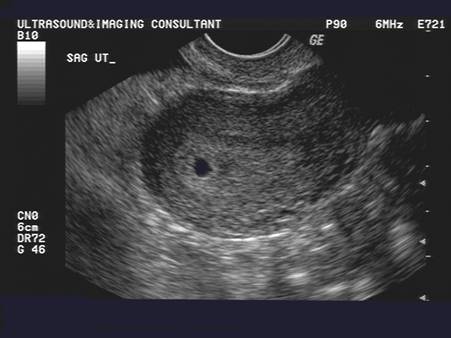

AKo vypadá prázdny gestačný vak?

@daniella30 to čo som ja videla na sone bola “bublinka” v tvare oválu alebo čo 🙈 vnútri nebolo ešte nič vidieť (cize ak to bol gestacny vak tak bez plodu) ... stres 🤦🏼♀️ A to som si tento mesiac povedala že sa nebudem na to moc sústrediť

@marinecka95 ale to je zas normalne, ze bol este prazdny, Ved je strasne skoro.

Ja som mala aj v 5+4tt este prazdnu bublinku, ani by som nesla ku gyn vtedy, len som odlietala na druhu stranu zemegule, tak som chcela potvrdit.